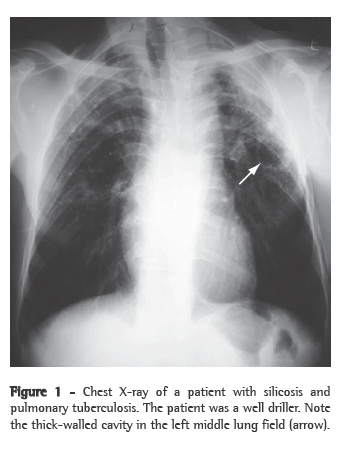

Patterns suggestive of silicotuberculosis have also been recognized on chest CT scans. The principal findings consistent with active tuberculosis superimposed on silicosis are thick-walled cavities (Figure 2), consolidations, images presenting a tree-in-bud pattern, nodular image asymmetry, and rapid disease progression.(26,28,29).